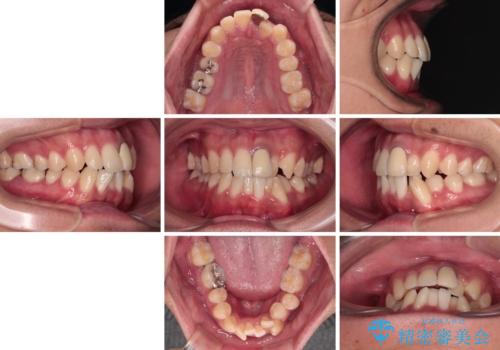

気になる前歯のデコボコと八重歯 ワイヤー矯正ですっきりと

- 前歯のデコボコや八重歯を気にして来院された患者様です。

他院でワイヤー矯正を行うつもりでいらっしゃったそうですが、通院が難しくなったとのことで当院での治療を希望されて来院されました。

上下ともに歯列幅が狭く、その影響でデコボコになっていたため、ワイヤー装置を用いて歯列を側方に拡大しながら、デコボコを解消していくこととしました。